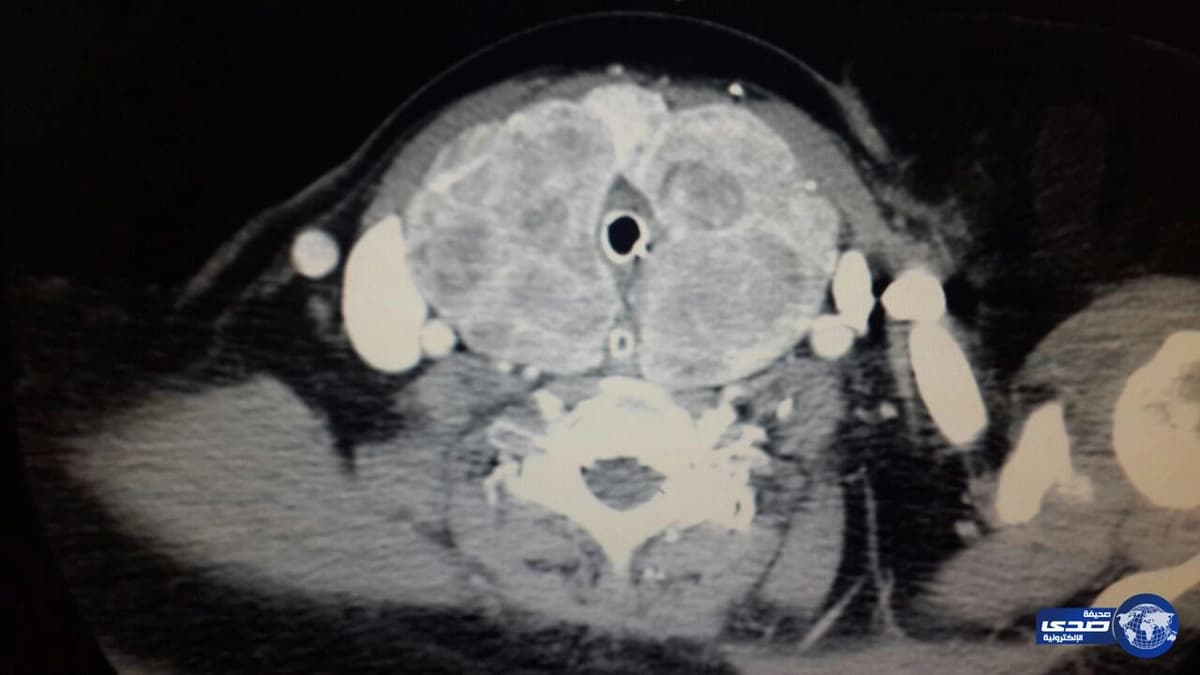

وكانت المريضة قد راجعت قسم الطوارئ وتم الكشف عليها واجراء اشعة مقطعية أظهرت أنها تعاني من أمراض مزمنة مثل داء السكري، وفرط توتر شرياني، ربو قصبي، وحادث وعائي دماغي، صاحب ذلك تغير في الصوت مع وجود صرير من جراء انسداد جزئي في الحنجرة يسبب صعوبة التنفس لهبوط الأكسجين بالدم وتم وضع المريضة على التنفس الاصطناعي بعد تنويمها بالعناية المركزة.